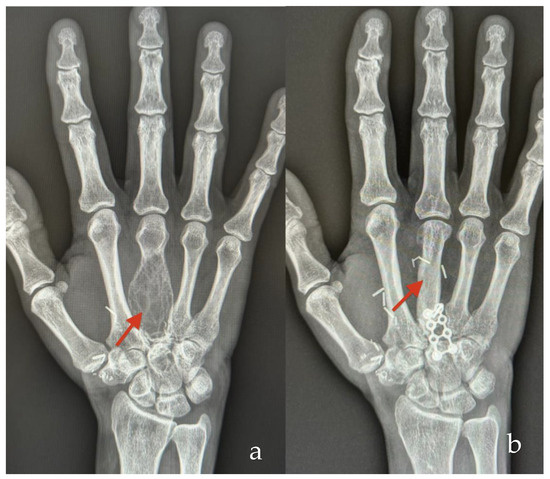

3.1.2. Case 2

| 5 | 47 | F | Metacarpal bone | Resection of  giant cell tumor  | Cortico-cancellous | 18 |